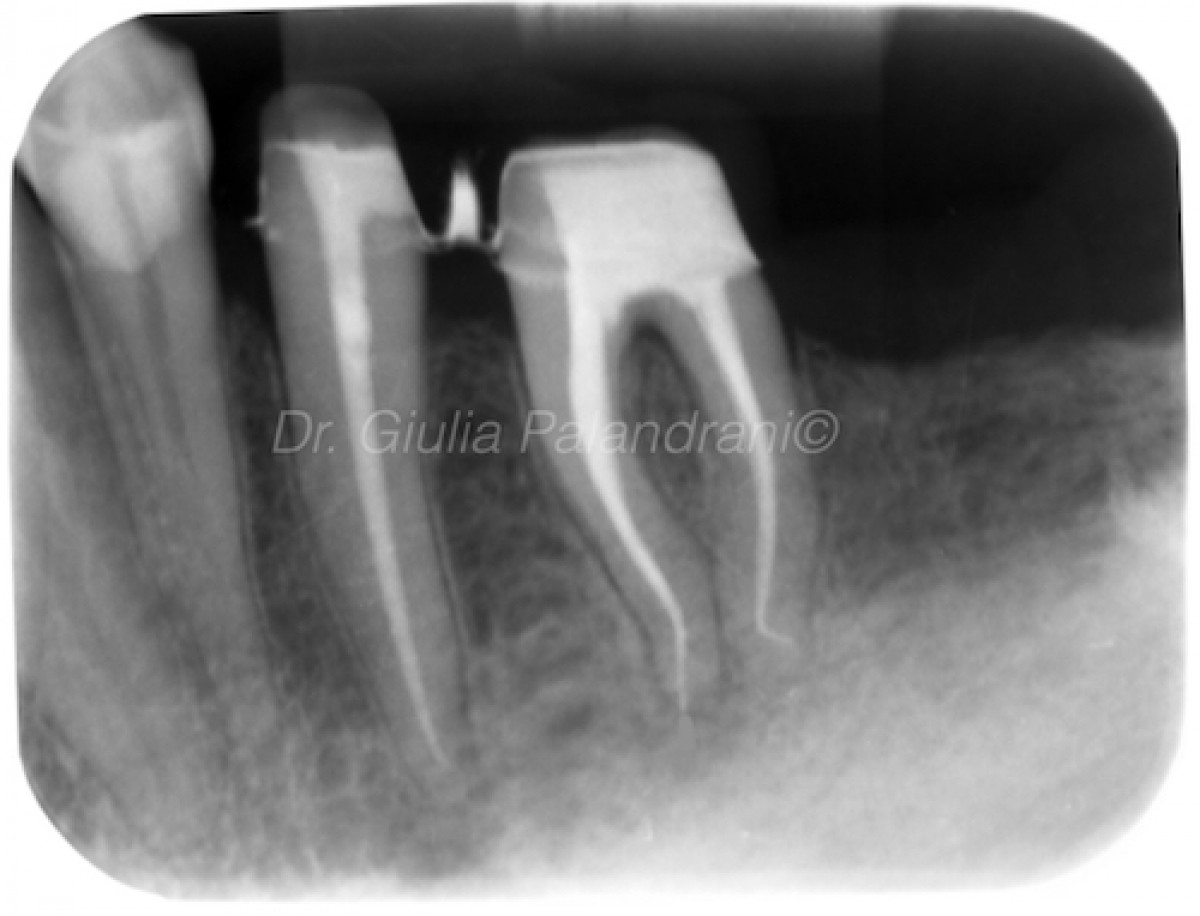

(A) Apical periodontitis in two lower incisor teeth. (B) Four months

(A) Apical periodontitis in two lower incisor teeth. (B) Four months What Is Apical Periodontitis In Dentistry several methods have been proposed for treating apical periodontitis,. Apical means relating to the apex, so. apical periodontitis is a chronic inflammatory disorder of periradicular tissues caused by aetiological agents of endodontic origin. apical periodontitis refers to the inflammation of the periodontium — the tissue that surrounds your teeth. apical periodontitis is the local inflammation of. What Is Apical Periodontitis In Dentistry.